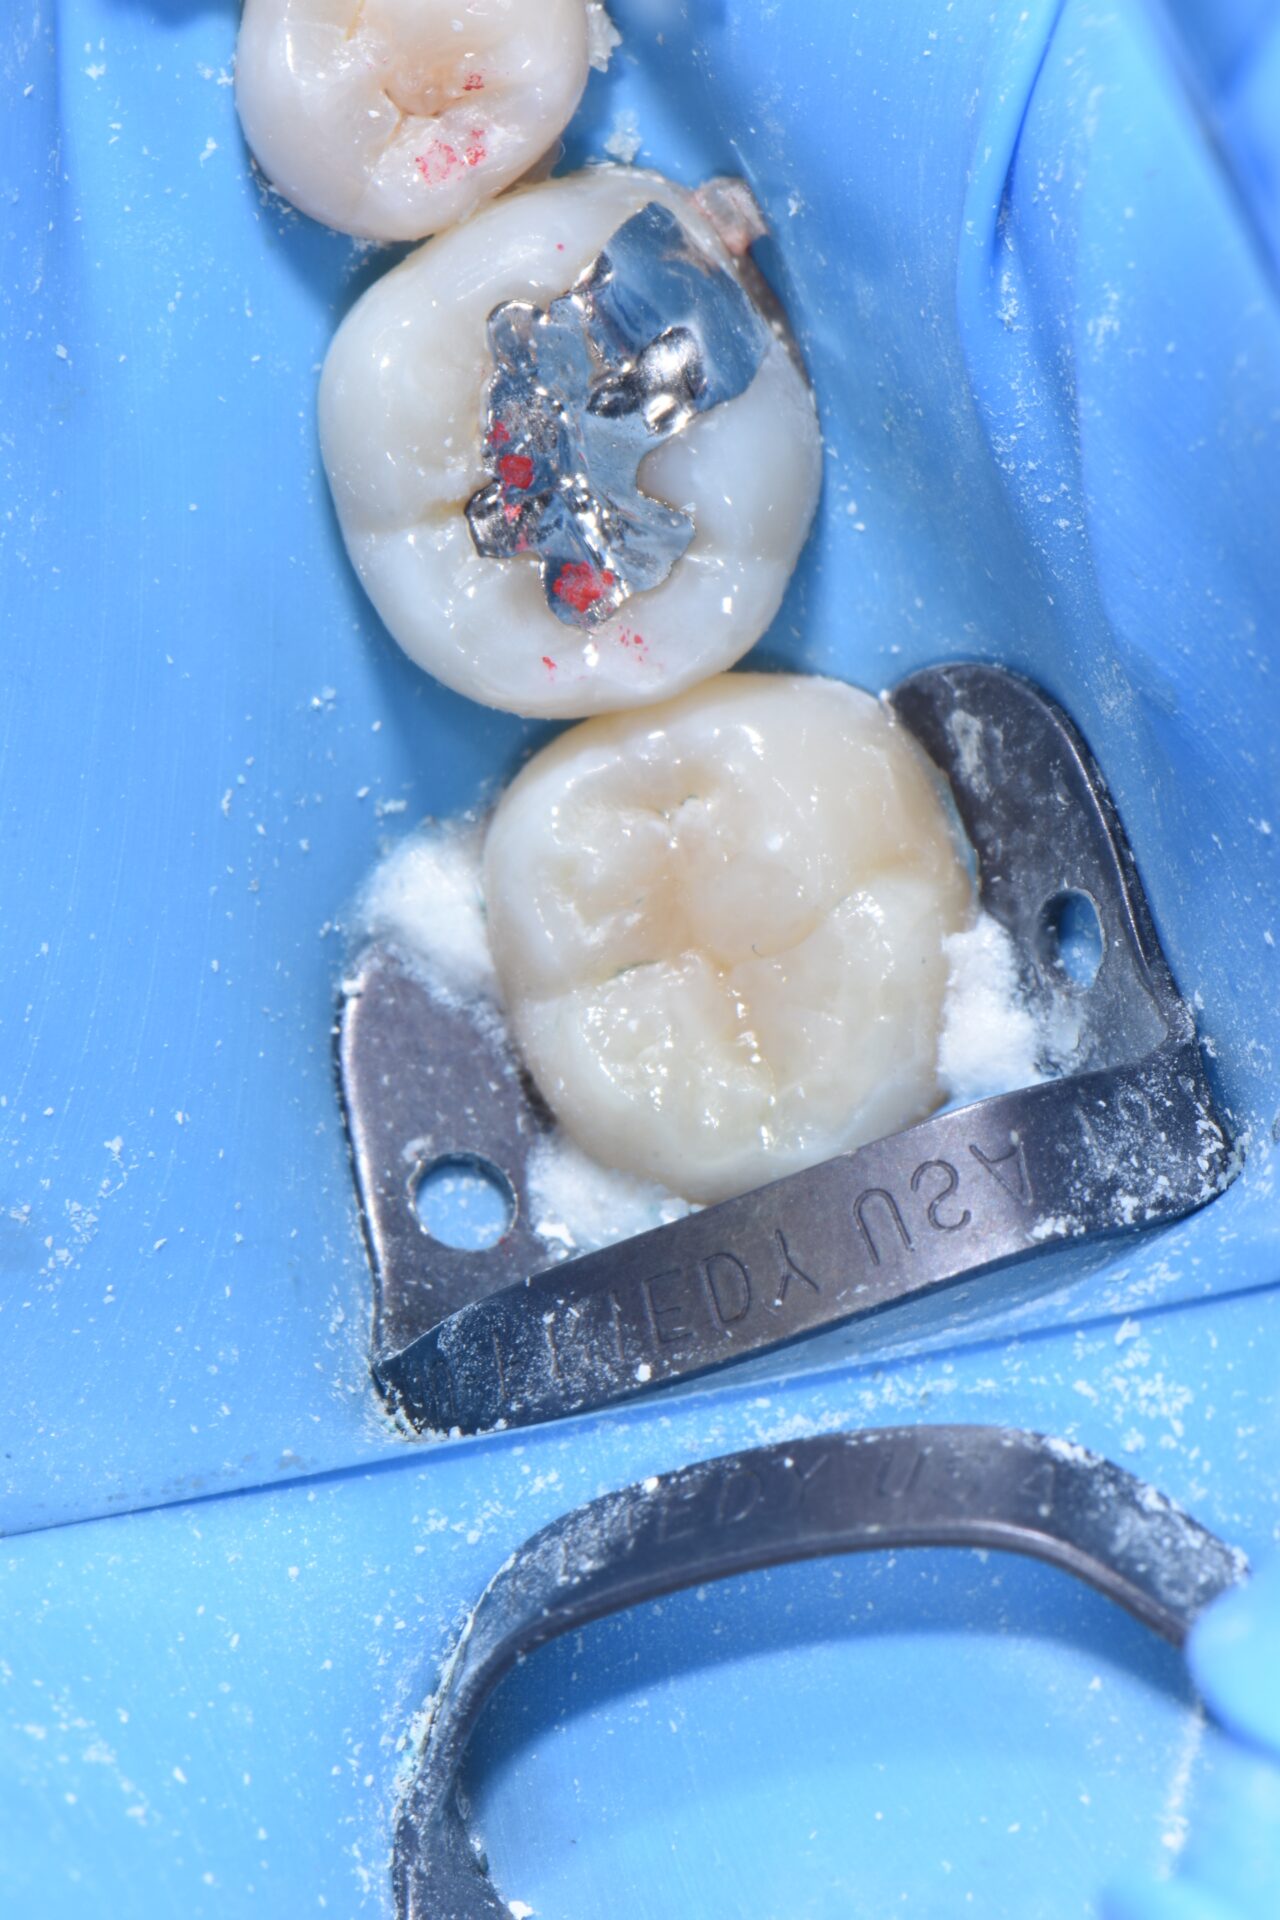

術後 通法に従い、ラバーダム防湿下でダイレクトボンディングにて修復治療